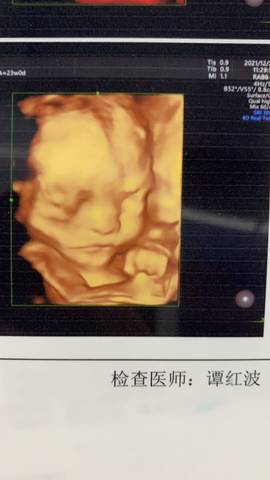

四维一次过!好奇男孩女孩!

爱生活的美 2021-12-27 12:41

journal_insert_pic_1686440180journal_insert_pic_1686440193journal_insert_pic_1686440215